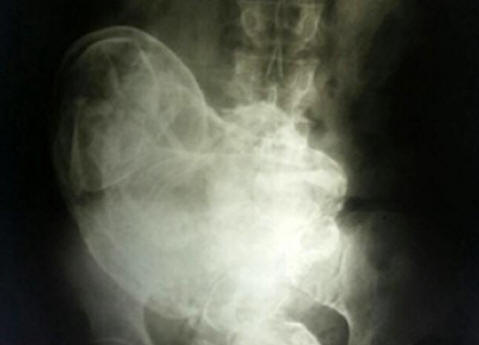

A 84 éves brazil nő méhében megfiatalodott magzat 44 éves. Ez akkor történt, amikor elviselhetetlen hasi fájdalom nő egy orvoshoz fordult, aki készítette X-ray. A képen egy megkövesedett embriót láttak. Ez a jelenség orvosi alkalmazásban kapott litopedion nevet kaptak. Lithopedion – egy megkövesedett méh magzat, amely meghalt a méhben vagy a hasban üreg, amelyen át meszesedtek. Ez ritka egy olyan jelenség, amely főként akkor fordul elő, amikor a magzat meghal méhen kívüli terhesség. Mivel nincs természetes hogy megszabaduljon az ilyen magzattól, a test kitenzi meszesedés, hogy megakadályozzák a magzati szövetek károsodását a hordozó testét. Az orvosok, akik megvizsgálták a nőt, megállapították hogy a magzat a terhesség 28. hetében halt meg. Ennek ellenére műtétből a beteg nem volt hajlandó eltávolítani. Marokkói eset Ez a jelenség nagyon ritka, ezért általában előfordulhat a történészek rögzítették. Ezt 2012-ben írják le. A belföldi illetőségű egy kis falu Casablanca közelében, Marokkó, három gyermek anyja, Zahra Abutalib utoljára 26 éves korában teherbe esett. Kilenc hónapos terhesség a magzat szövődmények nélkül elhaladt. A kórházban azonban tanúvá vált egy kórházi szobatárs halála, egy fiatal anya, aki meghalt az operációs asztalon császármetszés eredményeként. nem sikerült megmentenie gyermekét. Attól tart, hogy egy ilyen sors előfordulhat elvárják tőle, hogy érzékeny Zahra, aki összegyűjti a dolgokat, elmenekült kórházak, úgy döntve, hogy otthon szülnek. A következő néhány évben Napok óta szörnyen szenvedett szülési fájdalmaktól, bár a régóta várt a gyermek soha nem lépett be a világba. Hamarosan teljesen leállt méhben mozogni, és a nő úgy döntött, hogy a baba “elaludt”. Zahra jól emlékezett az “alvó baba” helyi mítoszára. Állítólag ha nem szülni fog, akkor egész életében megvédi anyja tiszteletét. Ezért nem különösen aggódik állapotát illetően, főleg a összehúzódások miatt már nem ismétlődik. Ez negyvenhat évig zajlott addig, amíg a közelmúltban, már 75 éves korában a fájdalom hirtelen nem tér vissza. Zahra orvosokhoz fordult. Ultrahang vizsgálat egy városi kórházban Rabat idegen nő jelenlétét mutatta a hasban testek, amelyek eredetét az orvosok nem tudták megmagyarázni. ez volt az eredmények alapján alaposabban megvizsgálta a testet mely szakértők arra a következtetésre jutottak, hogy a test szilárd tömege A Zahra nem más, mint egy megkövesedett gyümölcs, amely a női test csodával csinálta egy szervet, ezért hosszú ideig nem idegen testnek tekintik. A műtét négy órán át tartott. Végül Dr. Taibi Kuazzani vezette orvoscsoportot sikerült kivonnia a nő testéből egy kicsit kettőnél nagyobb magzatot kilogramm, hosszúság pedig 42 centiméter. Szóval, majdnem fél évszázaddal végül született Zahra gyermeke.

Fotó nyílt forrásból A litopedion a nő testében alakul ki magzati halál esetén, általában egy magzat terhesség, bár vannak olyan esetek, amikor kialakul a méhben. Az anya teste a halott gyermeket idegen testnek tekinti, és a védő reakció eredményeként a magzat mumifikálódik. első egy ilyen eset részletes leírása 1582-ben nyúlik vissza, amikor egy bizonyos Egy francia orvos 68 éves nő boncolásakor fedezte fel megkövesedett gyümölcs, amely 40 éven át az anya méhében maradt. Egész életen át tartó terhesség Az orvosi statisztikák szerint A “kőgyerekek” egy személyben maradhatnak, amíg hosszú ideig. És a 46 év semmi esetre sem a határ. Tehát, 2009 januárjában egy kórház a kínai Huangiaotang városban 92 éves helyi lett Huang Yuijun rezidens, aki nagyon súlyos fájdalomról panaszkodott a gyomor. Mi volt az orvosok meglepetése, amikor rájöttek egy idős nő … terhes! Sőt, hosszú ideig terhes – 60 éves! Csodálatos története, a The Sun szerint, elkezdődött vissza 1948-ban. Aztán az orvosok elmondták Huang-nak, hogy a magzat már meghalt születése a méhében. Ennek eltávolításához egy műveletre volt szükség mely orvosok helyi pénznemben 150 eurónak megfelelő összeget kértek dollárt. Az árakat meghallva Huang egyszerűen megfordult és elment. “Ez az akkoriban sok pénz volt, mondja a nő, több a családom összes tagja néhány év alatt keresett. Ezért i Nem csináltam semmit, úgy döntöttem, hogy figyelmen kívül hagyom az orvosi diagnózist. ” A “figyelmen kívül hagyás” évtizedekig folytatódott, amíg az elhunyt Magyarországon nem volt Méhében a gyermek nem emlékeztette magát újra. “Nem tudtam elhinni saját szemébe, amikor rájött, hogy méhében Yuijun van egy gyermek ”- mondja Dr. Liu An Bin a Gwingshengi Kórházból. – érte 40 éves orvosi gyakorlatom nem más Nem láttam semmi furcsa vagy meglepő dolgot. ” Szülészeti és nőgyógyászati kórház Xu Xiang Ming hozzáteszi: “Általában egy halott magzat felrobban. De ebben az esetben foglalkozunk ritka esemény. Még nem világos, hogy Yuijun asszony hogyan egész idő alatt jó állapotban maradt. “További kérdések a mai nap leghosszabb oka az orvostudomány történetében a 93 éves lisszaboni lakos, Maria Romandes terhessége, aki 1996 – ban a kórházba ment, súlyos fájdalommal panaszkodva a gyomor. Mi volt az orvosok meglepetése, amikor rájöttek egy idős nő terhes, két mumifikált magzattal 72 évben! Nagymama emlékeztet arra, hogy 1924-ben beteg lett beteg, egyre súlyosabb volt. Ugyanakkor megállást figyeltünk meg menstruációs ciklus. A nő rájött, hogy valamilyen problémája van női oldalról, de mivel nem éreztem különösebben súlyos fájdalmakat, Az orvoshoz sem mentem. Egy idő után hányinger elmúlt, és Maria egészen 1996 tavaszáig panaszkodott egészsége miatt évben. Az orvosok, miután meghatározták a “betegség” okát, azonnal műtétet végeztek és eltávolítottak két jól megőrzött szádot az ikrek. A szakértők szerint kudarcba haltak meg teljesítmény. A táplálkozás hiánya vált ennek oka Maria Romandes teste nem dobta el őket időben.